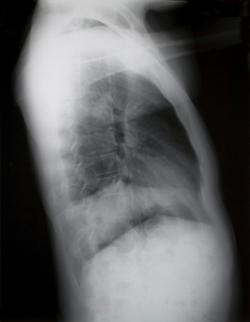

Also in the construction industry has the risk to develop silicosis (the black lung - as you can see on the picture) increased. This is due to the increasing use of more powerful grinding and milling equipment within concrete work, which release a large amount of very fine dust.